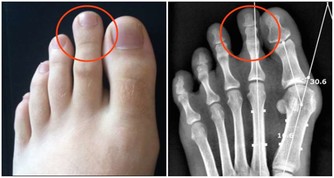

很多人飽受膝關節疼痛折磨甚至影響到日常生活。以下四種人需要重視這篇文章:關節嘎巴嘎巴響的人;腿疼的人;上下樓腿疼、膝蓋疼,有骨刺;O型腿的。

上樓疼、下樓疼、上下樓沒勁髕骨老化、膝關節炎症、髕骨軟化,積水、長骨刺、咔咔作響這種現象都會迅速好起來!